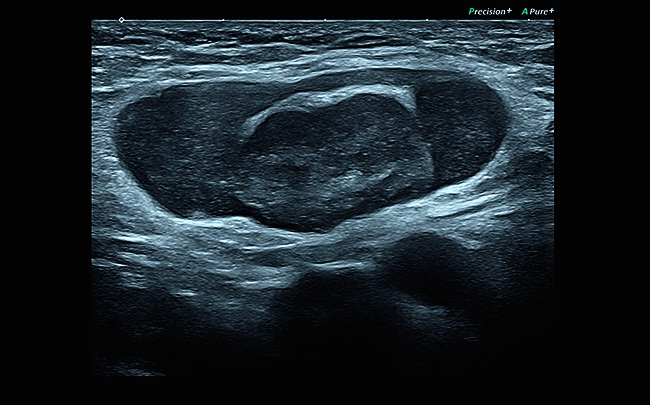

• Технология MicroPure для обнаружения небольших концентраций солей кальция

Компрессионная эластография

Эта методика выявления опухоли, построенная на анализе отличий модулей продольной упругости, была принята в качестве общего стандарта и применяется для детального исследования поверхностно расположенных органов. С ее помощью вы сможете добиться детального и по-настоящему качественного результата проводимого исследования.